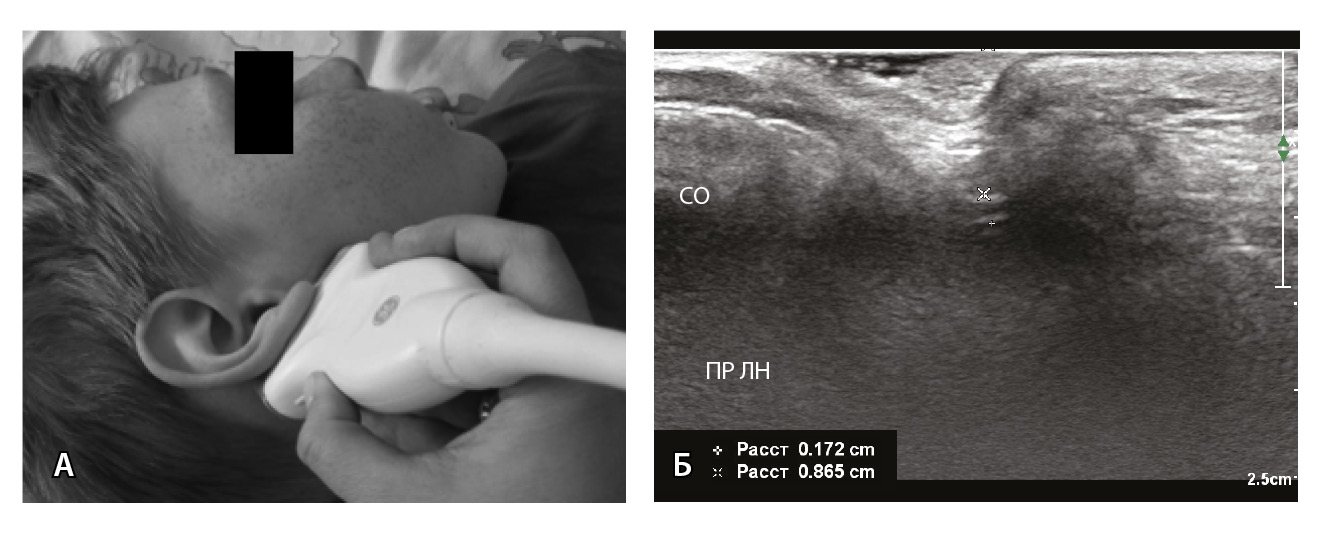

ЭНМГ и периферическая ТМС лицевого нерва выполняются по стандартным методикам. Оцениваются показатели мигательного рефлекса, амплитуды М-ответов и ВМО носовой мышцы (m. nasalis) здоровой и пораженной стороны, их соотношение в виде ЭНМГ- и ТМС-коэффициентов. С помощью УЗИ не только определяется диаметр ЛН пораженной и здоровой стороны, но также проводится сравнение показателей глубины залегания ЛН в области шилососцевидного отверстия с двух сторон. УЗИ лицевого нерва выполняется с использованием высокочастотного линейного датчика 18 МГц, в норме в области выхода из шилососцевидного отверстия нерв представлен трубчатой гипоэхогенной структурой с гиперэхогенными стенками. Методика сбора УЗ-показателей (диаметра и глубины залегания ЛН) представлена на рис. 4. Для сбора усредненных значений исследование проводится в наиболее толстой части ЛН с включением гиперэхогенных стенок при трехкратном повторном измерении.

Рис. 4. Измерение диаметра и глубины залегания лицевого нерва: А – положение ультразвукового датчика; Б – схема измерения диаметра и глубины залегания лицевого нерва. Белая линия – диаметр (1,72 мм), зеленая линия – глубина залегания (8,65 мм); ПР ЛН – правый лицевой нерв, СО – сосцевидный отросток